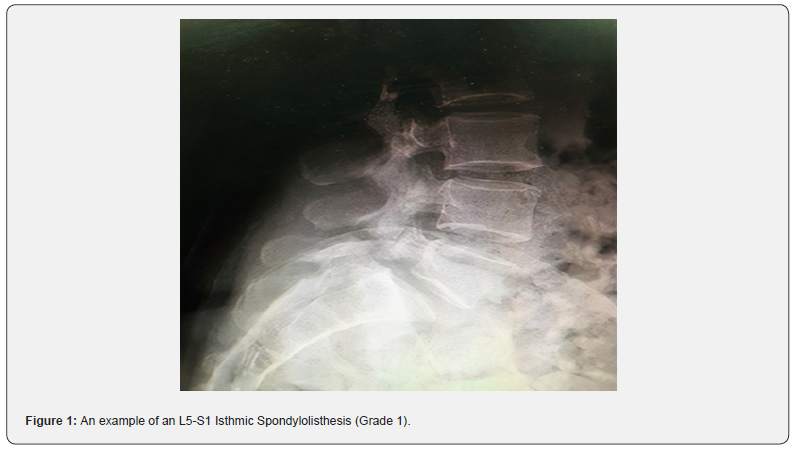

The patient population that was under investigation, which resulted in a total of 1,000, included 61 cases with a mean age of ∼55 years (54.7) that were identified with spondylolisthesis. With a confidence interval of 95% (0.119), the prevalence of spondylolisthesis was 6.1% (±0.119) of the true value. In addition, the Male to Female ratio that has been reported in the study is 20:41 i.e. (1:2). Females are twice as likely to have this disorder than males. The highest frequency of spondylolisthesis was degenerative spondylolisthesis (66%), followed by isthmic spondylolisthesis (30%), and dysoplastic spondylolisthesis (5%) (Figure 3). The vertebral level L5-S1 was the most common level involved (56%) with L4-L5 level involved in 37% (Figure 4) in comparison to most studies concerning spondylolisthesis [2-4] (Figures 1 & 2). Lower back pain was reported in 92% of those with spondylolisthesis, with a confidence interval of 95% (1.679%) and ~92% (91.80%) ± 1.679% from the true interval). Unfortunately, there is inconclusive evidence of a correlation between spondylolisthesis and occupation. The prevalence ratio was not calculated, as there were insufficient data. The study’s main aim was to not only determine the prevalence and link lower back pain to this disorder but also to identify any other associated risk factors that might have an impact on this disorder. There seems to be no exact or definite indication for a single disease/ disorder that may be considered a factor that might result in the development of spondylolisthesis. However, (CI 95%) 13 out of 61 (21 ± 2.11%) patients with spondylolisthesis also had a history of hypertension, (CI 95%) 16 out of 61 (26.23% ± 1.95%) patients with spondylolisthesis who had a history of Diabetes Mellitus, and (CI 95%) 7 of the 61 (11.475 ± 2.27%) patients had hypothyroidism, but the question is, are these chronic illnesses the reason for the increased risk of this disorder? Because of the nature of these systemic illnesses, they can affect the prognosis of this disorder; however, are critical risk factors that have a distinct effect on this specific disorder. Simply put, there is little evidence to support this theory. Regarding the patients’ lifestyle, since Kuwaiti population is one of the top ten ranked countries in regards to obesity and being overweight, most patients that were studied are not exercising as an average individual, which is 150 min of aerobic exercise per week. The majority of patients lived a sedentary lifestyle in addition to a poor nutritional diet.

Various aspects were considered when developing the methodology. The inclusion criteria played a significant role in differentiating this study from others. An effort was made to incorporate all types of spondylolisthesis, and not restricting the age limit, to obtain an overview of the actual prevalence of spondylolisthesis. In addition, other factors in the methodology that were considered were the use of standing radiographs as a means to confirm the diagnosis in comparison to MRI or CT scans. The reasoning behind this was that radiographs (anterior/ posterior and lateral X-rays) were more sensitive in the ability to pick up a grade 1 spondylolisthesis (Meyerding classification of 0-25%) [11] versus other modalities of investigations that required the patient to lie down, limiting the opportunity to establish a proper diagnosis.